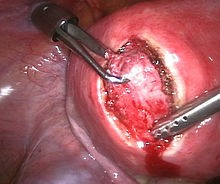

Treatment of an intramural fibroid bylaparoscopic surgery |

Myomectomy is a surgery to remove one or more fibroids. It is usually recommended when more conservative treatment options fail for women who want fertility preserving surgery or who want to retain the uterus.